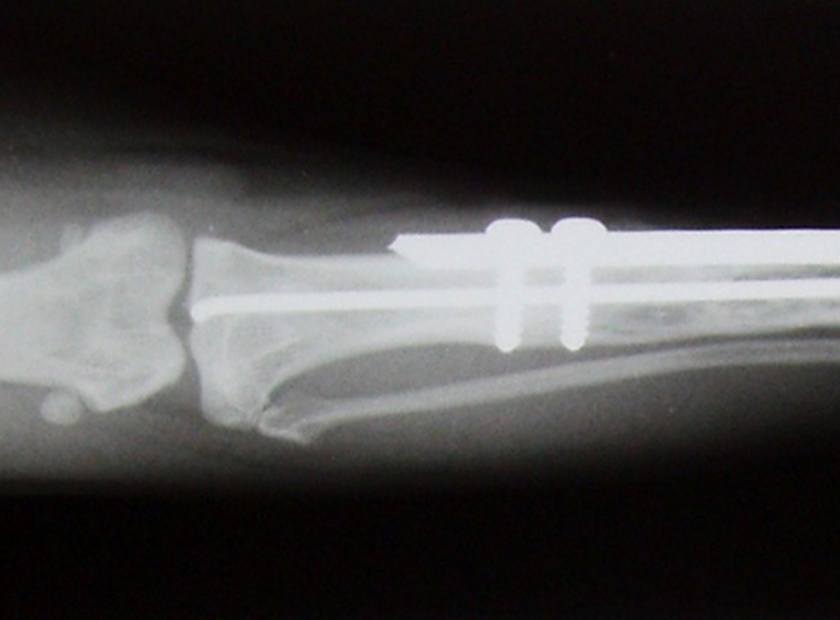

- Gelenksdyplasien wie HD, ED

Die Tierphysiotherapie umfasst im orthopädischen Bereich sowohl die prophylaktische Anwendung, die Therapie bei akuten Erkrankungen wie auch die Vor- und Nachsorge bei operativen Eingriffen (siehe auch "vor & nach Operationen").